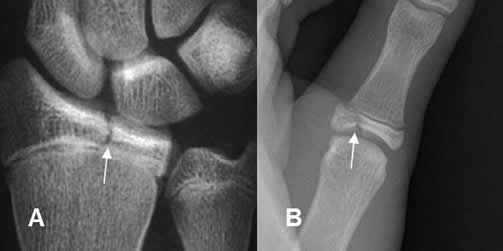

Fig 74 A. Salter tipo III.

A y B: Rx AP. Fracturas verticales en las epífisis del radio y el dedo, por lesiones tipo III.